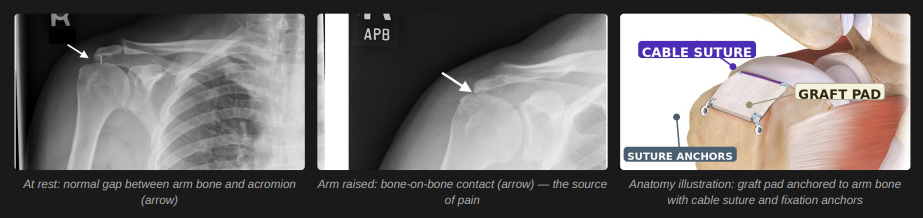

When a rotator cuff tear is too large to repair with stitches, the tendons can no longer hold your arm bone in place. As you raise your arm, the ball of the shoulder presses directly against the bone above it — causing pain with every movement.

- Biologic Tuberoplasty (ABT): A thin 3mm pad of donor tissue is anchored over the top of your arm bone. It cushions the joint, stops bone-on-bone contact, and over several months is replaced by your own permanent fibrous tissue. This is not a dissolving implant — it becomes a lasting part of your shoulder.

- Rotator Cable Reconstruction: The rotator cable — a thick band of tissue along the back edge of the cuff that acts like a suspension bridge, distributing forces across the shoulder — is repaired at the same time. This reduces stress on the graft and improves long-term stability.